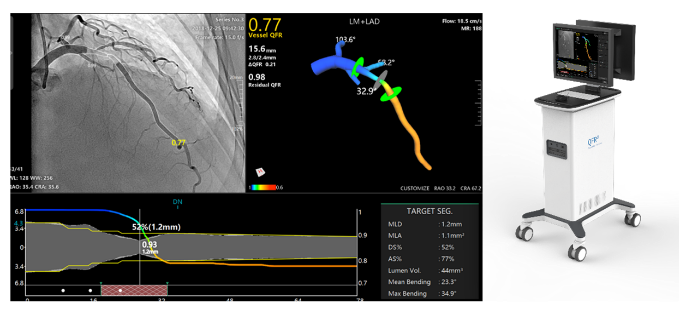

涂圣贤团队研制了一种基于冠脉影像评估血管生理功能的定量血流储备分数检测仪。系统可安装在医院介入导管室,通过网络获取导管室造影机采集的造影影像或血管内成像影像,实现快速冠状动脉三维重建与血流储备分数计算(含QFR、OFR与UFR),用于在线判断重建血管的解剖参数与功能缺血状况,以优化支架植入手术。

QFR界面示意